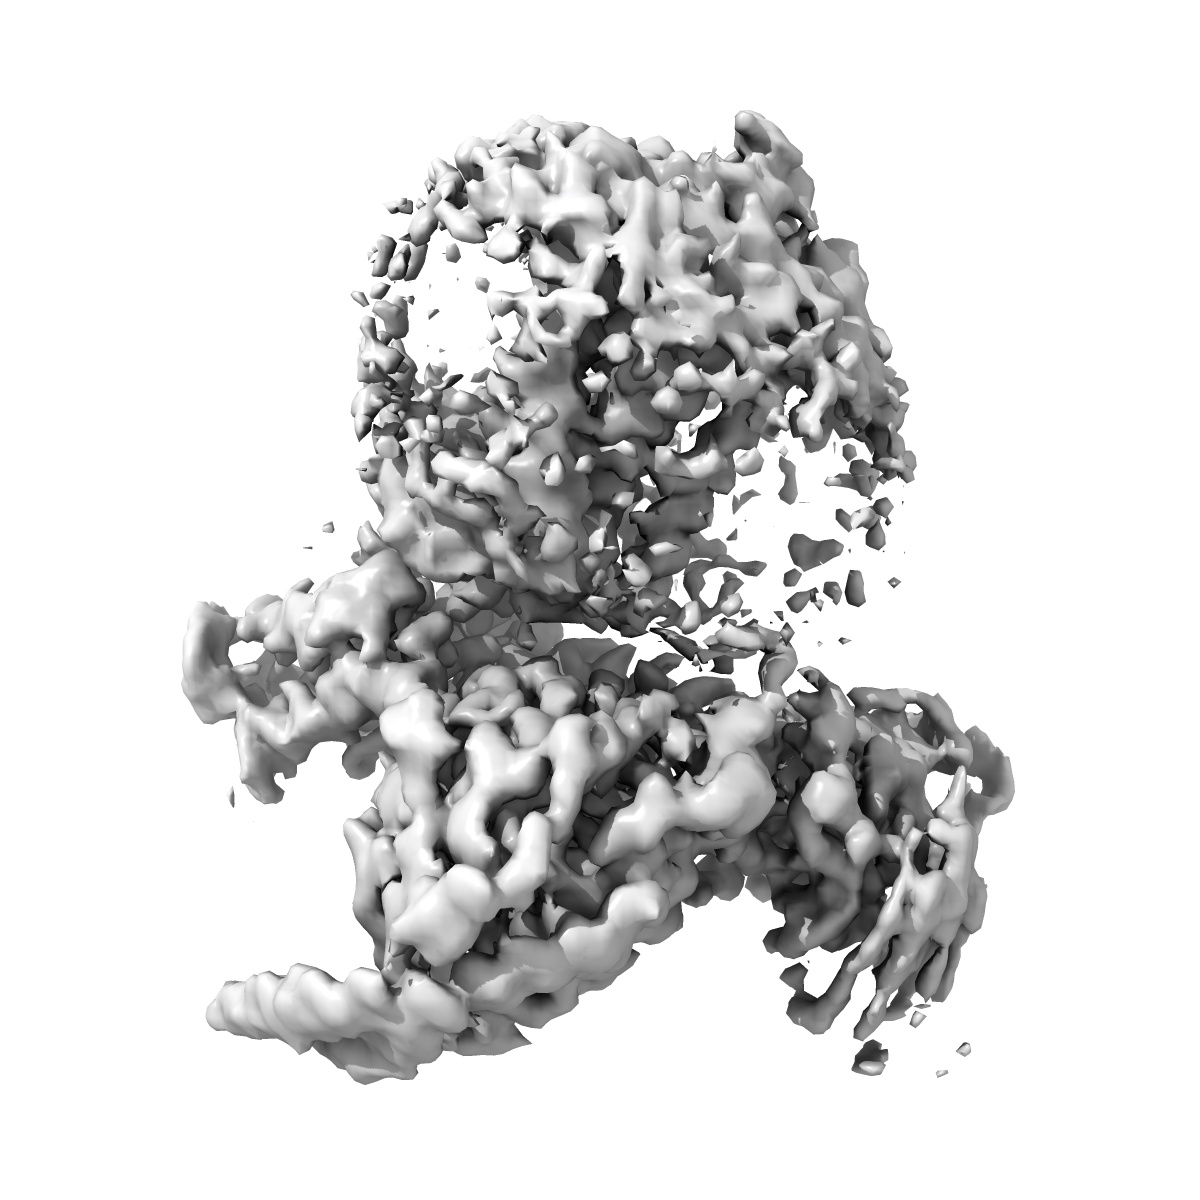

Structural basis of D9-THC analog activity at the Cannabinoid 1 receptor

Sample: HU210/CB1/Gi1 signaling complex

Structural basis of Delta 9 -THC analog activity at the Cannabinoid 1 receptor.